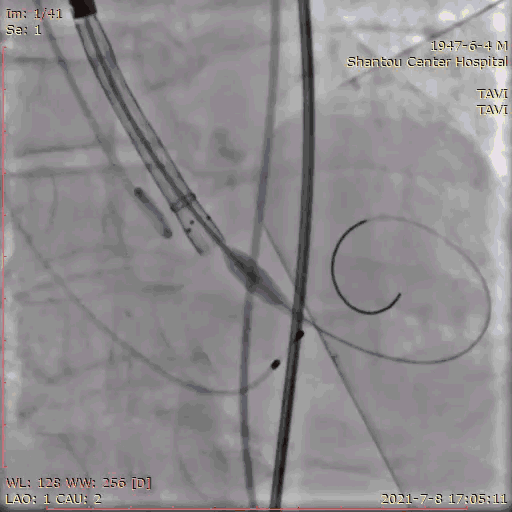

输送系统定位,标准位置释放

120bpm起搏

25球囊后扩